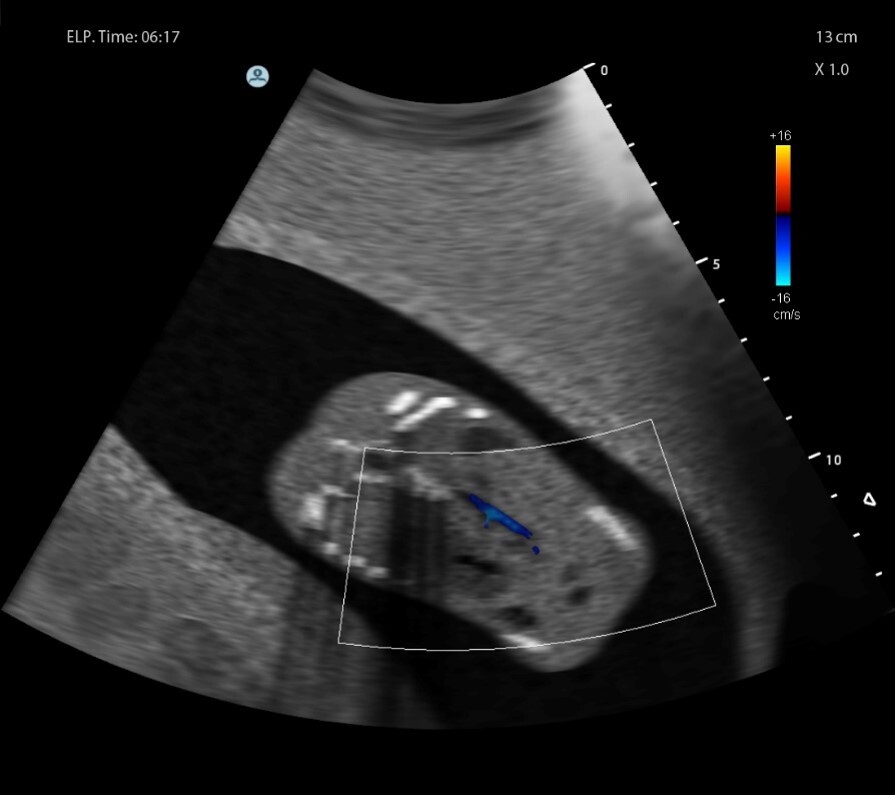

Q

What pathology is seen here?

A

Ectopic Kidney